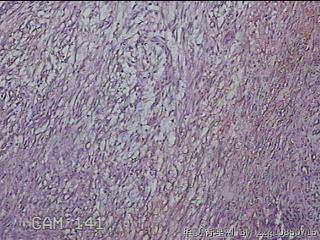

左肘部包块

性别

男

年龄

39

临床诊断

左肘部肿物:炎性脂肪瘤

一般病史

发现左肘部肿物1周。

标本名称

大体所见

灰白粉红色组织2x1.8x0.3㎝一团,表面结节状,光滑,切面灰白粉红色,质软。

图1

纤维组织细胞瘤

有外伤史吗,考虑结节性筋膜炎。

首先考虑结节性筋膜炎。

梭形细胞肿瘤,待免疫组化